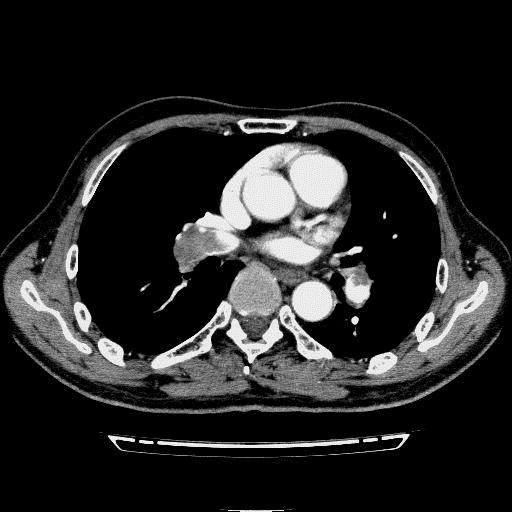

问题 病历摘要: 患者女性,83岁,活动后气促10天,伴心悸、咳嗽,咳少许白粘痰,感左侧胸痛,呈压榨样,与呼吸有关,但无放射痛,并发热,体温最高37.9℃,无明显规律性,无咯血、畏寒等。既往有系统性红斑狼疮病史,有吸烟史20年,已经戒烟20年。1月前始自觉双下肢易疲劳,但活动不受限。体查:T37.7℃,左肺可闻及啸鸣音和少许细湿啰音,心率123bpm,律齐,P2>A2,未闻及杂音。双下肢无水肿。 急性巨块型肺栓塞的诊断标准有哪些?

选项 A.体循环动脉血压<90mmHg,或较基础血压植下降幅度≧40mmHg,持续15min以上 B.二个或二个以上叶肺肺动脉完全栓塞 C.主肺动脉干栓塞50%以上 D.除外新发生的心律失常、低血容量或感染中毒症所致的血压下降 E.二个或二个以上段肺动脉完全栓塞 F.超声心动图见右心室运动功能减弱

答案 AD